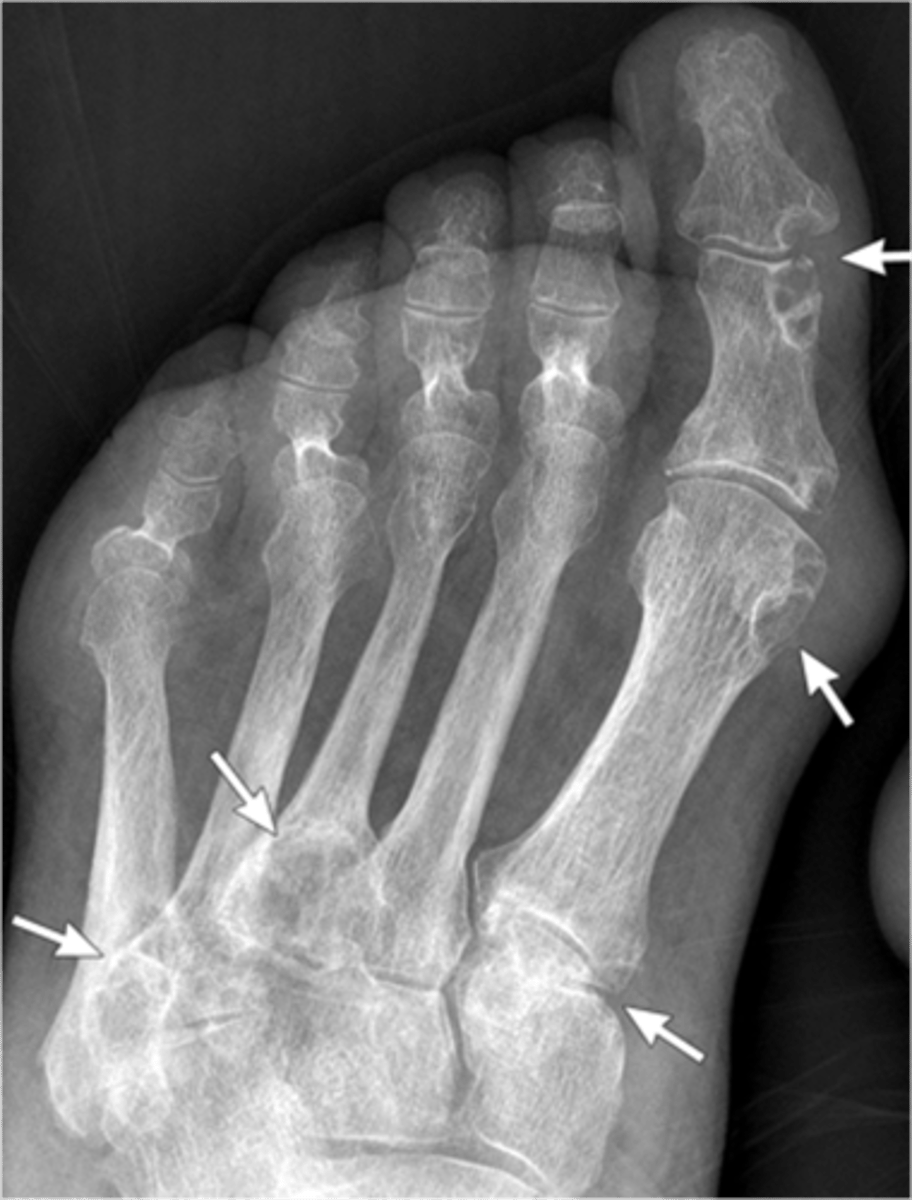

- Dense soft tissue tophi (swelling)

- Bone erosions

- Overhanging margin sign

- Secondary degeneration

- 1st MTP MC joint